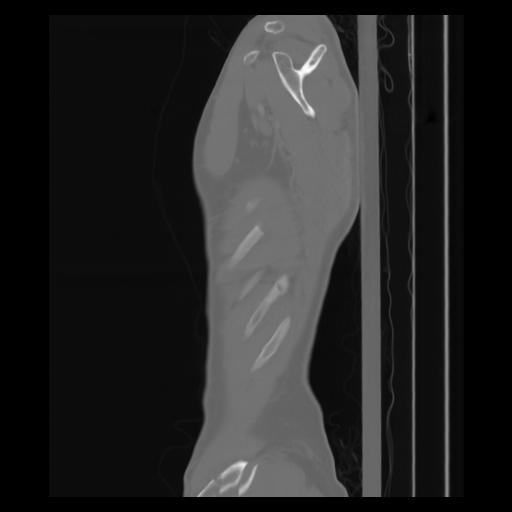

30 CUERPO,CE,Sagittal,3.000,CUERPO,Sagittal,